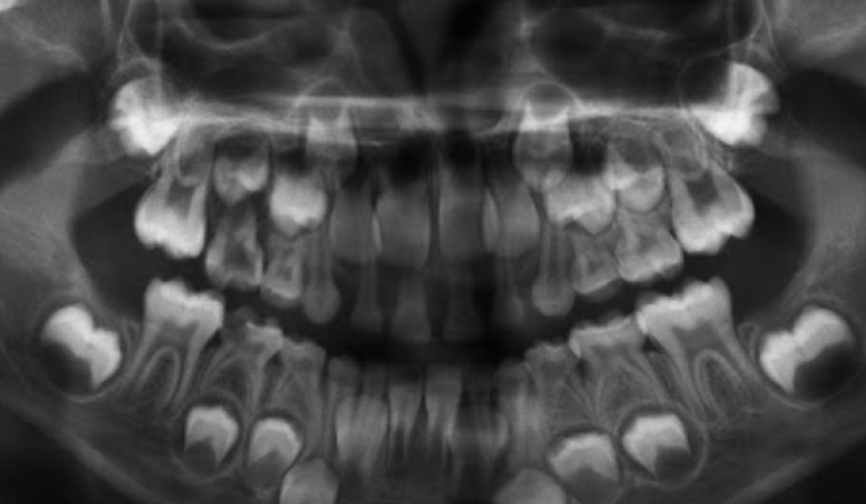

1.lower adult CI there? YES, so def 6-7

1. Upper Ad. Ci there? NO, so either 6-7 or under

Last molar crown not really formed so 6?

NOTE- THE 8’s - crown starts developing at 9 yo.